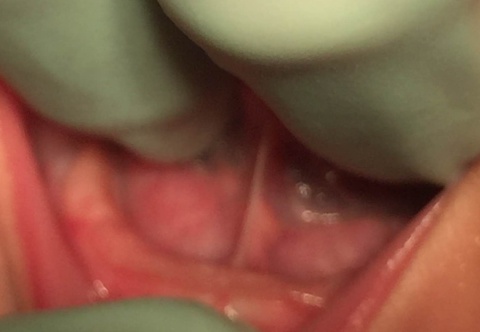

Type 2 Ankyloglossia